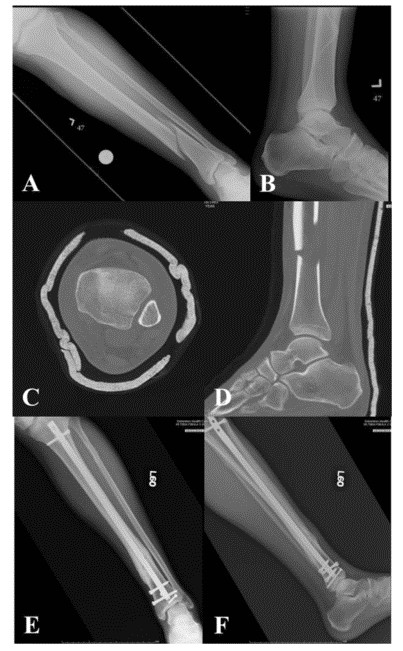

Сообщается о высоком проценте переломов нижней средней трети большеберцовой кости с переломами лодыжки. При использовании традиционной компьютерной томографии 43 % переломов средней и нижней трети большеберцовой кости сопровождались переломами голеностопного сустава, большинство из которых требовало хирургического лечения. Наиболее частым типом перелома был спиральный перелом нижней средней трети дистального отдела большеберцовой кости, связанный с переломом задней лодыжки с небольшим или несмещенным смещением (рис. 2). Из-за небольшого смещения связанного перелома лодыжки только 45 % повреждений можно обнаружить на обзорных рентгенограммах лодыжки. Таким образом, при наличии перелома нижней и средней части большеберцовой кости следует уделять особое внимание рутинному компьютерному сканированию голеностопного сустава (рис. 3).

Рисунок 3. Спиральный перелом AF средней и нижней трети левой большеберцовой кости (AB) на предоперационных рентгенограммах; (CD) предоперационная КТ, показывающая перелом задней лодыжки без смещения; (EF) демонстрирует плавное заживление перелома большеберцовой кости и лодыжки.